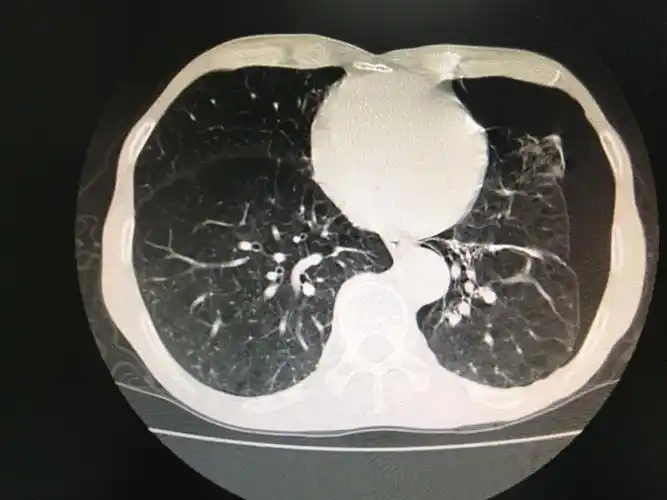

多发巨大肺大疱并自发性气胸病人1例

右肺下叶巨大肺大泡,弥漫性肺气肿肺大泡是一种不可逆转的肺部病损,故

双肺肺气肿伴右肺巨大肺大泡.